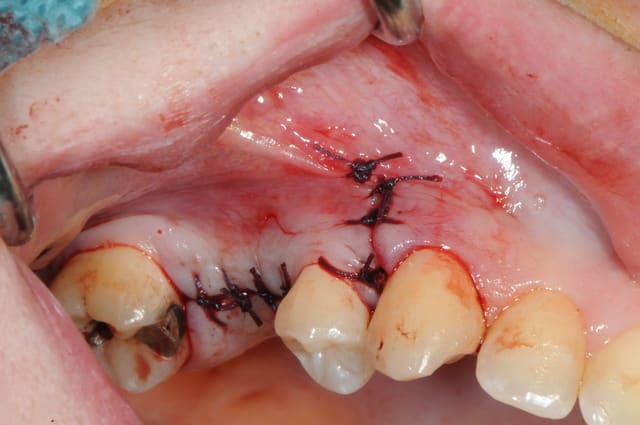

je sais pas si c'est un produit miracle, mais pour les sinus lift, c'est fantastique.

l'autre avantage est de ne pas avoir à mettre de membrane de recouvrement.

quasiment 6 mois entre les deux interventions (sinus lift et mise à jour)

c'est surtout la qualité des trabéculations osseuses qui m'interpelle.

d'habitude, on voit toujours un peu de particules, ici, c'est vraiment top.

Je suis en tout point d'accord avec toi : ce qui est vraiment intéressant, ce sont les trabéculations osseuses obtenues après cicatrisation.

très convaincant Thomas! et les photos toujours bien nettes.

je crois que c'est la première fois que je vois une cliché radio à quelques mois post-op avec ce matériau et le résultat semble excellent.